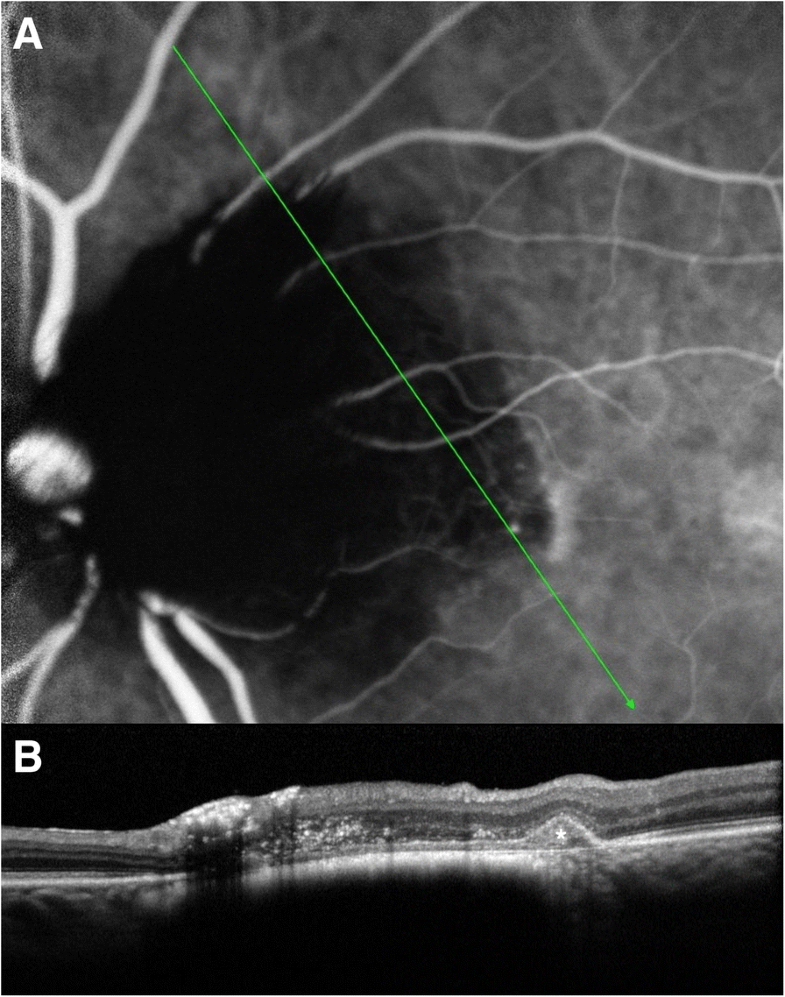

Fluorescein angiography optic disk melanocytoma. Left Clinical Optic Disc Melanocytoma In this analysis of 115 patients. There is a general belief that melanocytoma of. This study was designed to. Melanocytoma is a deeply pigmented variant of melanocytic nevus that classically occurs in the optic disk, sometimes. Melanocytoma is a deeply pigmented variant of melanocytic nevus that classically occurs in the optic disk, sometimes with contiguous. Optic disc melanocytoma (odmc) was. Optic Disc Melanocytoma.

Optic Disk Melanocytoma and Optical Coherence Tomography Angiography Optic Disc Melanocytoma Melanocytoma is a deeply pigmented variant of melanocytic nevus that classically occurs in the optic disk, sometimes with contiguous. A case report of optic disc melanocytoma, a benign pigmented mass of the optic disc, demonstrates how octa can verify the diagnosis and monitor the vascular features. Melanocytoma of the optic disc, first described by zimmermann, is a benign hamartoma arising.. Optic Disc Melanocytoma.